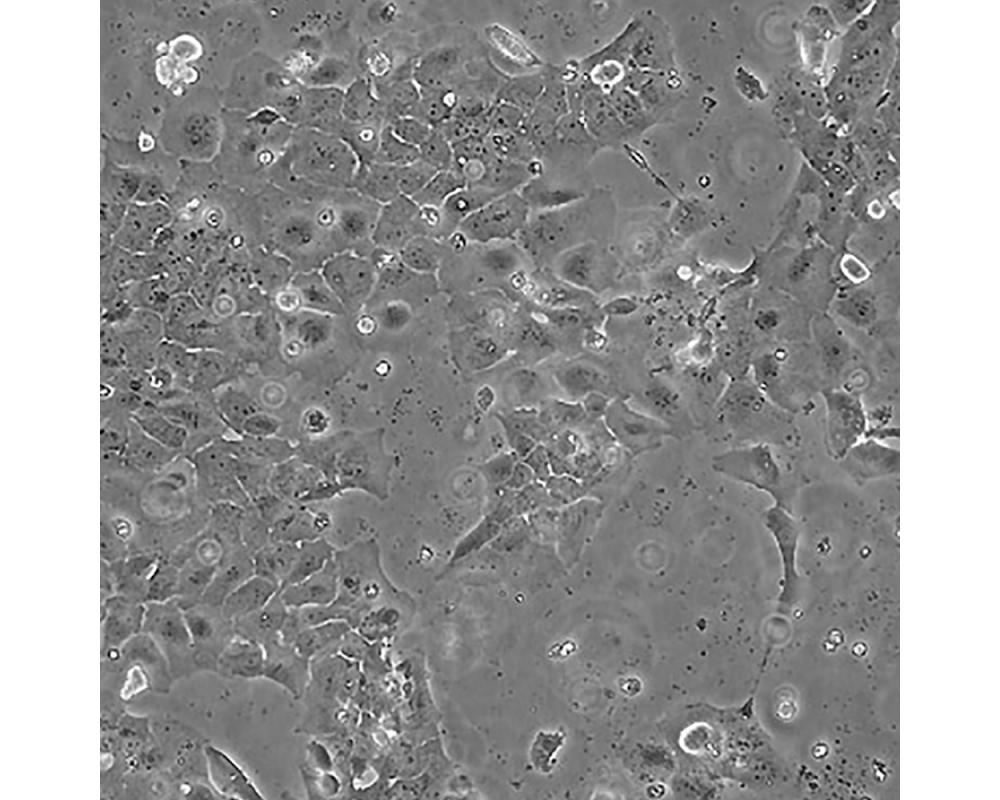

CAOV-3

中文名稱 人卵巢癌細(xì)胞

組織來源 卵巢癌;女性

形態(tài)特征 上皮樣

生長特性 貼壁生長

特征特性 該細(xì)胞1976年建系,源自一位54歲白人女性的卵巢腺癌組織。

培養(yǎng)條件 DMEM(高糖)+10%FBS

傳代方法 1:3傳代,2~3天換液一次